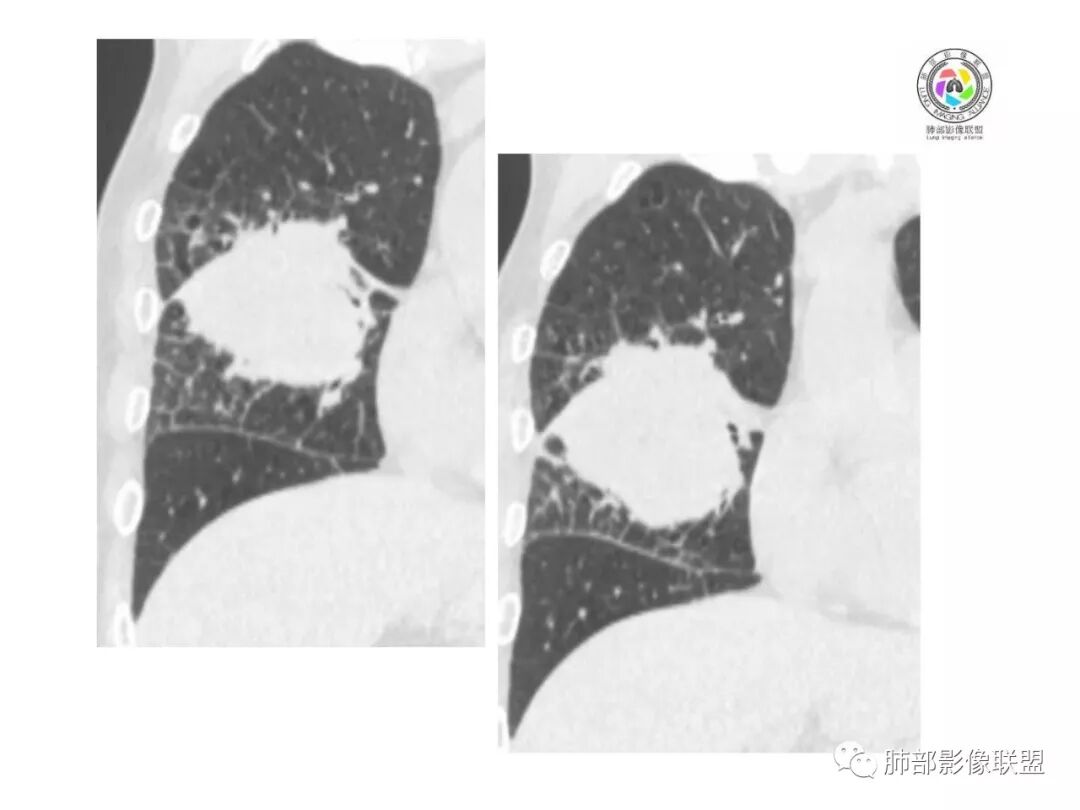

患者中老年男性,体检发现肺部占位。

胸CT:右肺中叶实性占位性病变,呈膨胀性生长,对斜裂明显挤压,右肺中叶外侧段阻塞,并在边缘可见分叶、毛刺、棘突样改变,胸膜牵拉;增强可见病灶明显强化,可见边缘模糊血管影,病灶内可见大片状低密度区,隆突下可见肿大淋巴结。

诊断考虑:恶性病变。

右肺跨上叶与中叶一实性肿块影,中叶外侧段支气管堵塞,肿块有明显分叶、毛刺、棘突样改变,胸膜牵拉,周围有小花小草;增强可见病灶明显强化,病灶内可见大片状低密度区,以外侧为主,隆突下可见肿大淋巴结,恶性,考虑鳞癌可能。

患者中老年男性,体检发现右肺占位。血常规轻度贫血,AFP、CEA正常,肝肾功能、血糖、血脂、心肌酶、电解质正常。胸部CT:右肺中叶巨大肿块灶,垮叶生长,可见分叶、毛刺、血管集束、支气管截断征象,远端周围可见小叶间隔增厚,增强轻度强化,内可见低密度坏死区,综合淋巴结肿大,且可见淋巴结内似低密度灶。综合考虑恶性,鳞癌并癌性淋巴管炎可能大。鉴别结核、腺癌。

胸CT:右肺中叶团块样实性占位,边缘膨隆,中叶外侧段阻塞,病灶可见深分叶、棘突,胸膜牵拉;增强不均匀强化,可见边缘模糊血管影,病灶内大片状低密度区,纵隔多发肿大淋巴结。

诊断考虑:恶性病变,鳞?大细胞?鉴别:TB